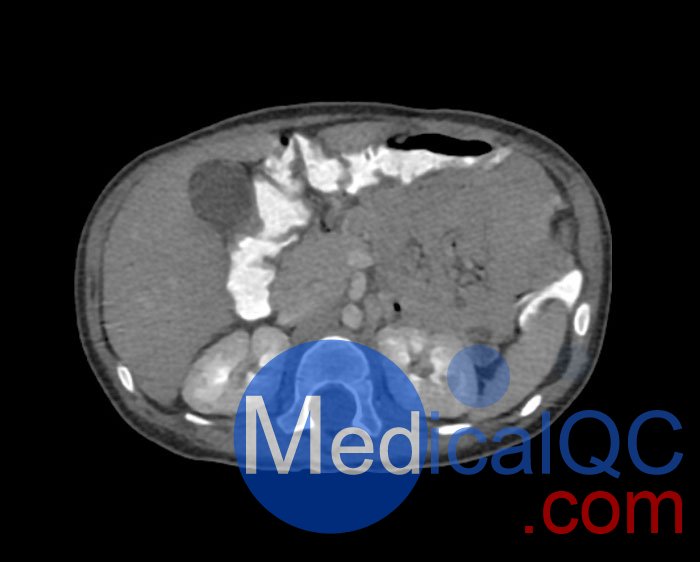

WEK58-03兒童軀干模型,WEK58-03兒童軀干模體模擬了 1 歲兒童的造影劑增強了門靜脈期的胸部、腹部和骨盆。它覆蓋了會陰的第六頸椎。結(jié)腸充滿造影劑,如直腸給藥后。

WEK58-03兒童軀干模型,WEK58-03兒童軀干模體提供了對軟組織和骨組織的詳細(xì)而逼真的模擬。包括肺在內(nèi)的空隙充滿了大約 -160HU的纖維素聚合物復(fù)合材料。

真實模擬脈管系統(tǒng)、骨骼和軟組織,包括肺、心臟、肝臟、膽囊、胰腺、脾臟、腎上腺、腎臟、胃、小腸、結(jié)腸和膀胱。

WEK58-03兒童軀干模型,WEK58-03兒童軀干模體成像效果圖: